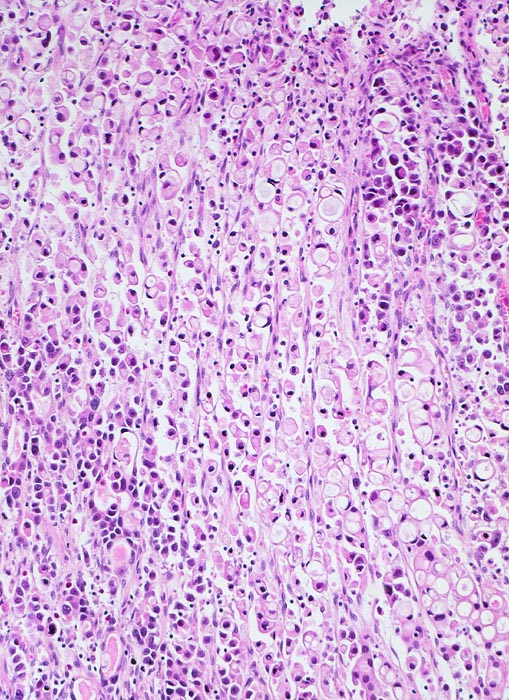

Siegelringzellkarzinom: Linitis plastica

Der Tumor besteht zu einem Grossteil aus Siegelringzellen mit unterschiedlich grossen Schleimvakuolen, die den Kern zur Seite drängen. Links unten im Bild bilden die Tumorzellen kleine Drüsenschläuche.

Magenkarzinome, die zu mindestens 50% aus Siegelringzellen bestehen, werden gemäss WHO als Siegelringzellkarzinome bezeichnet.